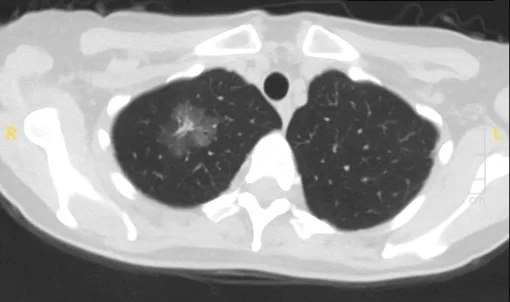

Those subtypes look different from one another on CT scans. “Indolent lesions tend to be characterized by nodules with a ground-glass appearance. Nodules that are more aggressive tend to have a solid appearance on imaging studies,” Dr. Powell says. “In the past, the management approach to those two types of nodules would have been the same. Now that we can distinguish subtypes based on imaging, we’re more comfortable following the low-risk lesions and intervening only when there has been a significant change.”

CT image of ground-glass and part-solid nodules taken in 2019

Same patient rescanned in 2023

Importantly, research also suggests that this watch-and-wait approach doesn’t increase risk to patients. “I’ve been monitoring some patients for 15 years with no changes to their indolent tumors,” Dr. Powell says. “And we’ve learned that when we do detect a change on imaging, we have sufficient time to intervene.”